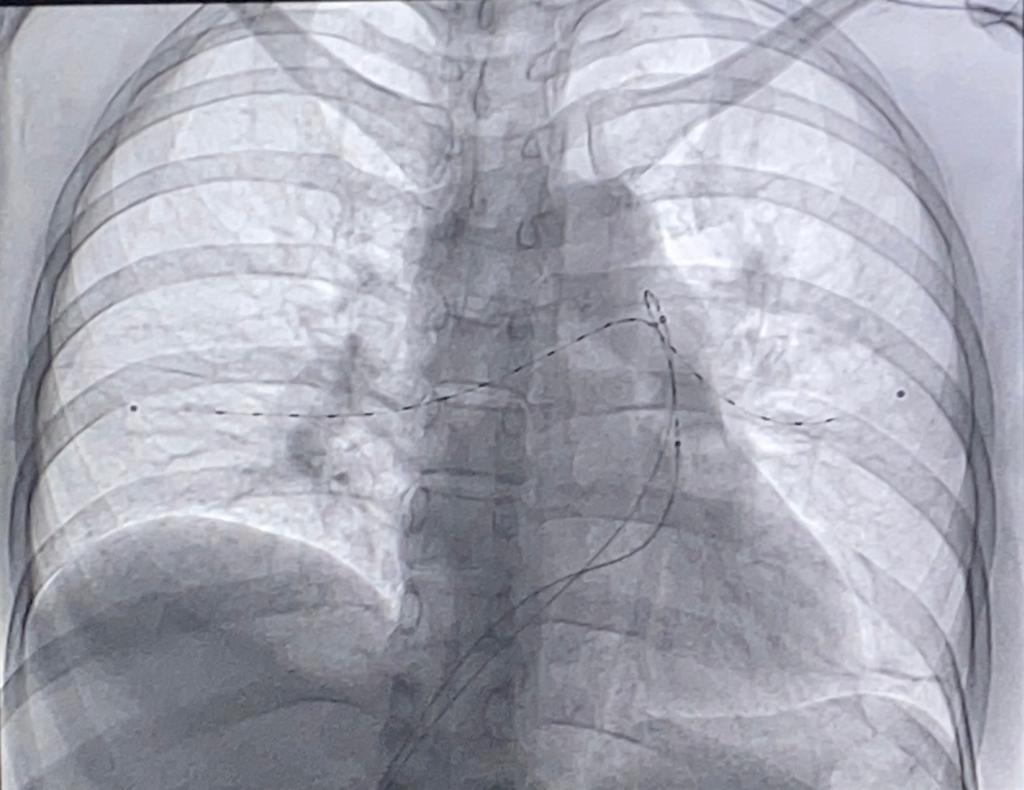

Fragmentación de trombo y trombo aspiración pulmonar, en tromboembolia pulmonar, por intervencionismo.

La fragmentación del trombo es un procedimiento invasivo realizado en unidades de estudios hemodinámicos que puede ser combinado con succión o no.